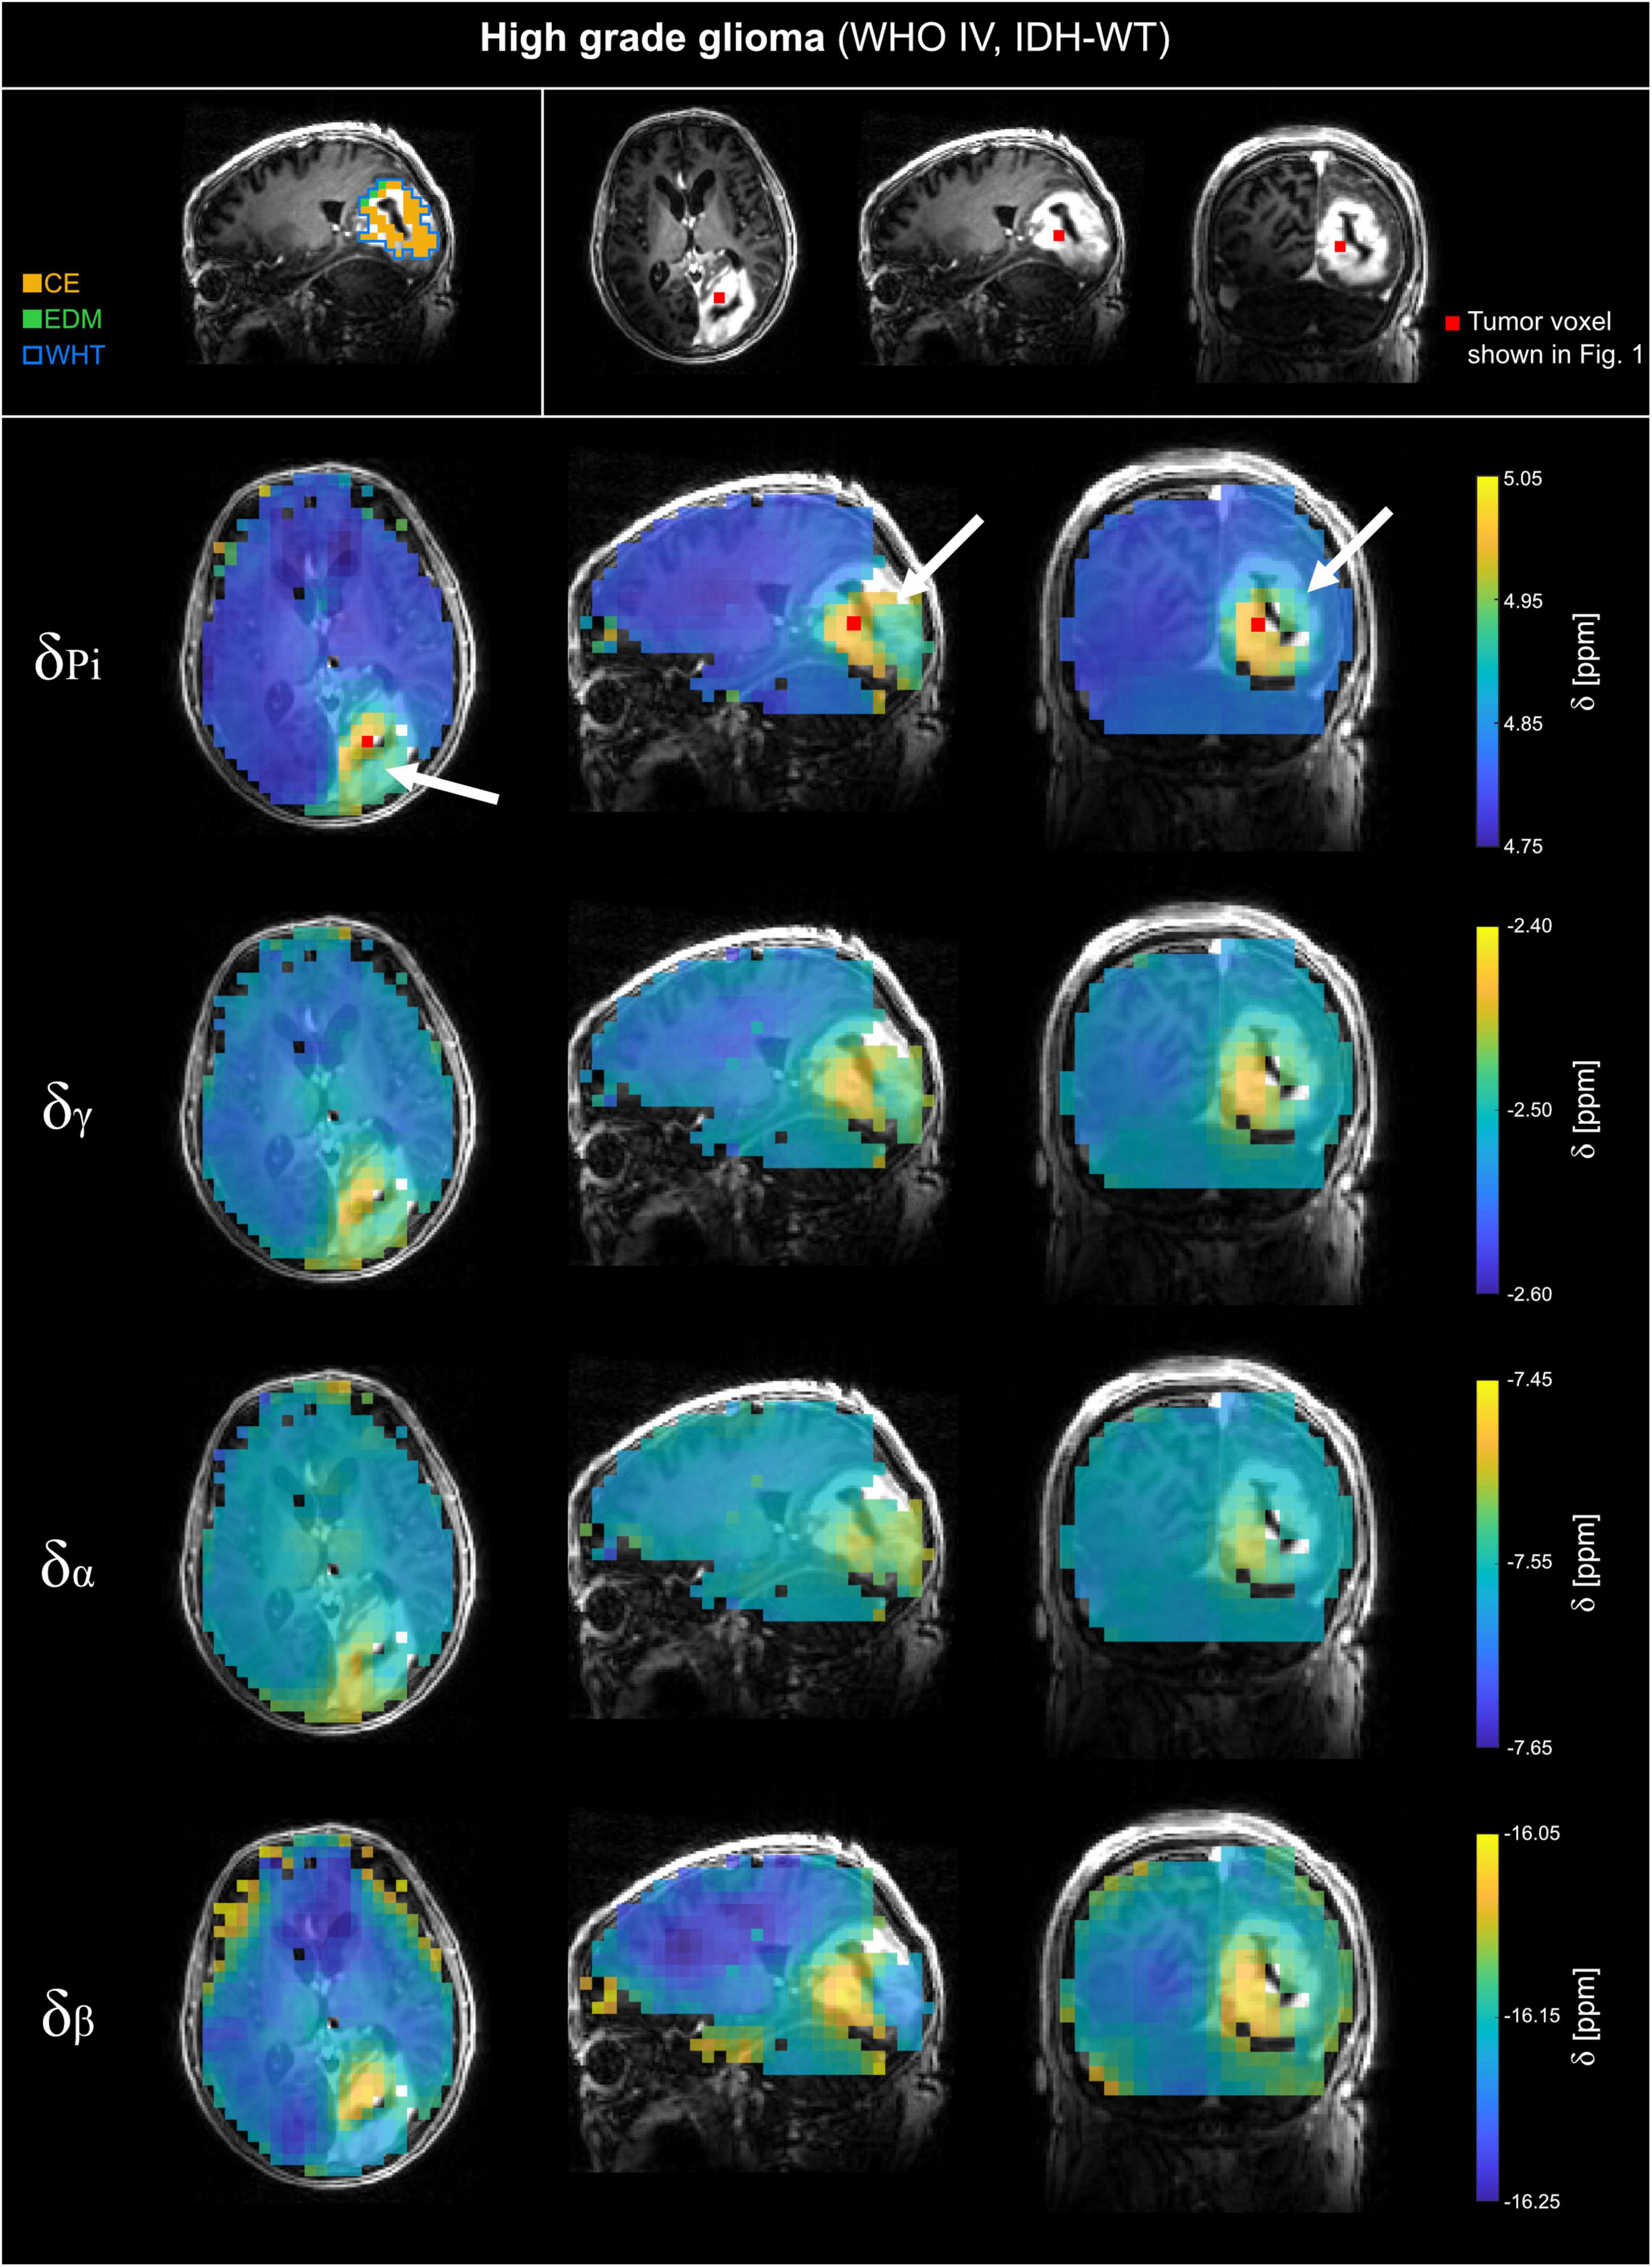

FIGURE 2

Volumetric maps of the quantified chemical shifts of inorganic phosphate (Pi) and ATP (γ-, α- and β-ATP) relative to phosphocreatine of a representative patient with high-grade glioma (WHO grade IV, IDH-WT; HGG). The 31P MRSI datasets were acquired at B0 = 7T with an isotropic, nominal spatial resolution of (12.5 mm)3 and spatially zero-filled with a factor of 2 before quantification. The position of the selected tumor voxel shown in Figure 1 is indicated as red box on the slices of the anatomical image. Voxels that were outside the tissue mask or have been excluded from further analysis based on the automated quality assurance were made transparent. On the top left, the regions of interests (ROI) used for further analysis are shown for a representative slice. For patients with HGG, the ROIs covering the whole tumor volume (WHT), the gadolinium contrast enhanced area (CE), and the edema (EDM) were analyzed. The position of the tumor is highlighted with a white arrow.

The analyzed 31P MRSI datasets from patients with glioma reveal differences in chemical shifts for different tissues, which are visible when comparing the acquired spectra (cf. Figure 1). The quantified chemical shifts of Pi and ATP (measured relative to PCr) show differences between tumor and healthy tissue (cf. Figures 1–3). The resonances of Pi, γ- and β-ATP obtained in tumor tissue are shifted downfield compared to those from healthy tissue. The α-ATP chemical shift shows minor differences between tumor and healthy tissue (maximal difference ≈ 0.05 ppm). For the chemical shifts of Pi, γ- and α-ATP, the difference between tumor and healthy tissue is smaller for the patient with low-grade glioma (LGG) than for the patient with high-grade glioma (HGG). Interestingly, this is not valid for the chemical shift of β-ATP, where the difference between tumor and healthy tissue of the patient with LGG (Figure 3), is comparable to the chemical shift difference for the patient with HGG (Figure 2). The difference in δβ between tumor and healthy tissue is up to 0.15 ppm for both patients. These qualitatively described observations are also confirmed in the following group analyses.

The comparison of the mean chemical shifts across the different tumor sub-compartments (Figure 4, left sections) shows particular patterns in the chemical shifts. For patients with HGG, δPi, δγ, δα and δβ are generally higher in the CE-ROI than in the EDM-ROI, with a significant difference for δPi (p = 0.014) and δγ (p = 0.004). For patients with LGG, δPi, δγ and δα are lower in the non-contrast enhanced ROI (LGG-NCE) compared to both HGG-GCE and HGG-EDM, but still higher than for healthy tissue. In contrast to that, for δβ, the shifts in the LGG-NCE ROI appear to be as high as the shifts in the HGG-CE ROI, supporting the observations from the representative datasets in Figures 1–3.